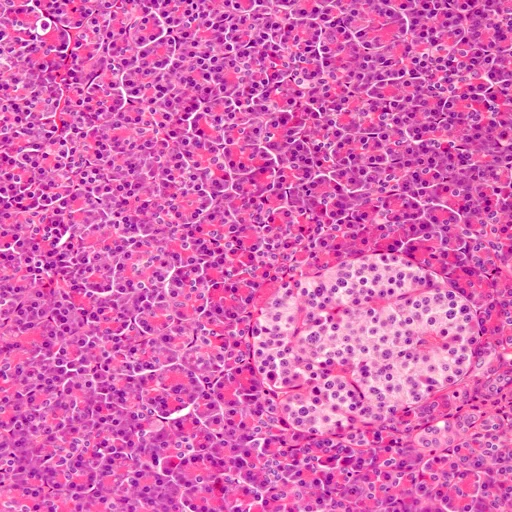

Histiocytose